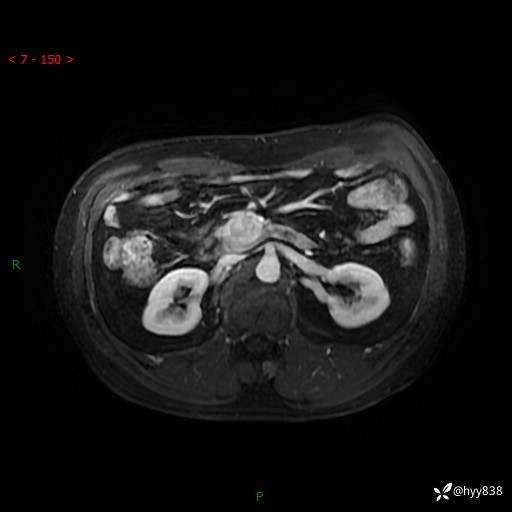

MRI(T1WI+T2WIfs+DWI)

增强